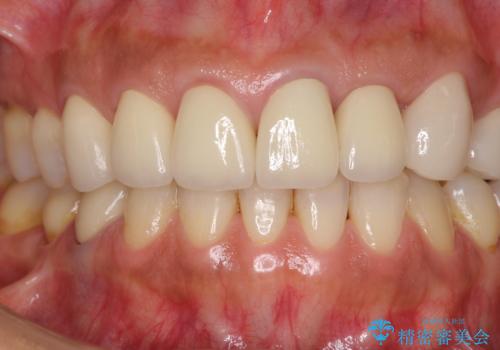

- 前歯の歯肉の高さが左右で異なっていることを気にして来院された患者様です。

歯肉レベルを調整するために歯周外科処置をおこない、その後にオールセラミッククラウンにて補綴することとしました。

処置後の痛みはあまり気にならず、歯肉位置の左右差もほとんどなくなり、患者様には大変満足していただきました。